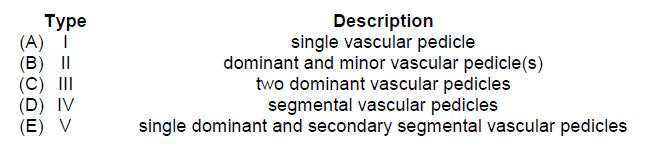

Mathes-Nahai vascular anatomy classification for muscle flaps:

I – Single dominant vascular pedicle

II – Single dominant vascular pedicle with secondary minor vascular pedicles

III – Codominant major vascular pedicles

IV – Multiple segmental vascular pedicles

V – Dominant vascular pedicle with segmental secondary pedicles that can supply muscle if dominant is divided

The correct response is Option D.

The sartorius muscle demonstrates a Mathes-Nahai Type IV vascular pattern with multiple segmental vascular pedicles. For this reason, it is important to preserve as many segmental pedicles as possible when transferring this flap. The sartorius flap is usually transferred as a distally based flap, and not a proximally based flap as presented in the clinical scenario. When based proximally, it is necessary to ligate multiple segmental pedicles to achieve an adequate arc of rotation, and this can lead to flap necrosis. When based distally, it is often necessary to divide 1 to 2 segmental pedicles superiorly to allow an adequate arc of rotation, but this usually does not compromise the flap. If there is any concern regarding flap perfusion, the pedicles can be temporarily clamped before division to assess the effects of pedicle ligation.

Examples of muscle flaps with the other Mathes-Nahai types of vascular pattern include the following:

Type I – tensor fascia lata

Type II – gracilis

Type III – gluteus maximus

Type V – latissimus dorsi